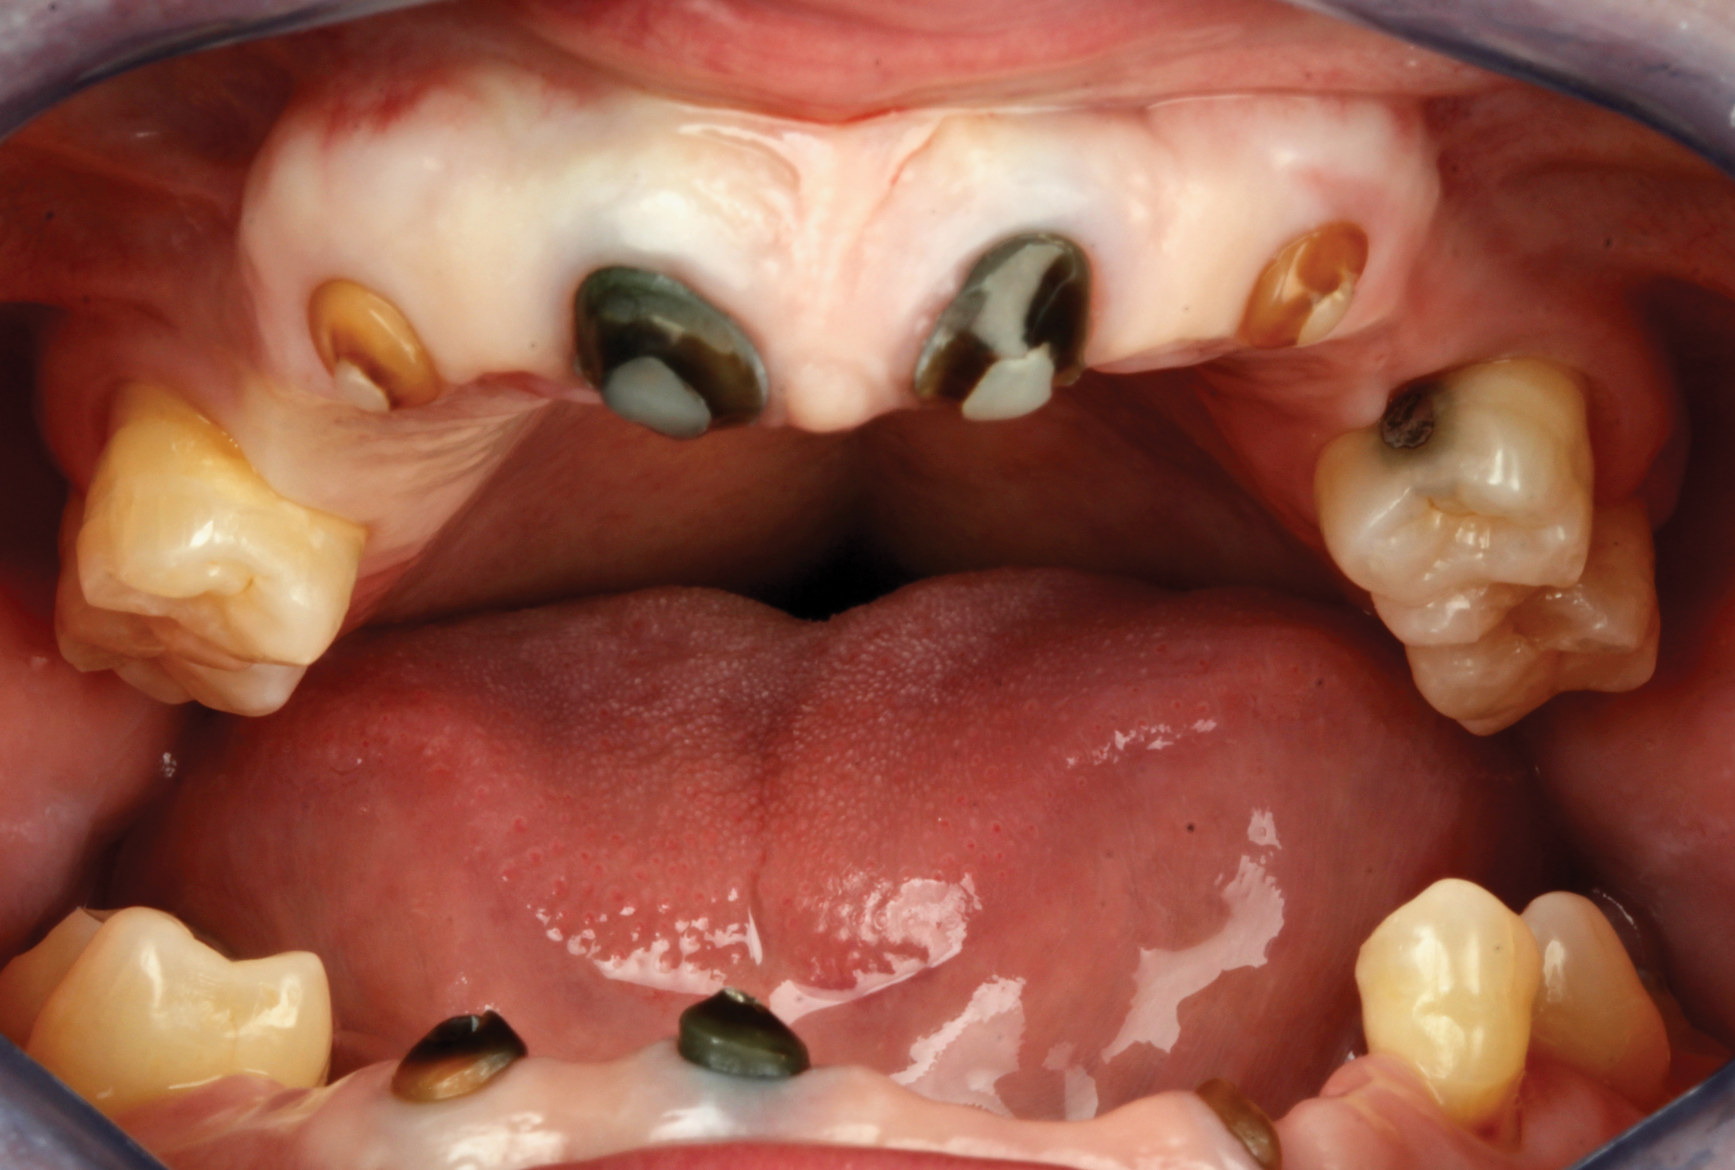

A fully integrated digital design was created focusing on the patient's desired outcomes of having a highly esthetic, natural-looking smile with ideal form and function that was as close to a natural dentition as possible. The smile design created using design software (3Shape Dental System, 3Shape, 3shape.com) and surface scanning images were merged with STL and CBCT files to engineer a virtual surgical plan, and then a pre-manufactured screw-retained fixed provisional restoration was fabricated-milled polymethyl methacrylate manufactured on a five-

axis mill (M5 Heavy Metal Milling Unit, Zirkonzahn, zirkonzahn.com)-that would function as the basis for the desired result (Figure 9 and Figure 10). The hypoplastic nature of the tissue and congenital deformity necessitated strict precision in the placement of the implants. Robotic guidance was employed to ensure the surgeon could make real-time plan adjustments if the bone or soft tissue contraindicated the treatment plan.

Fig 9. Presurgical proposed implant positions in digital scan with proposed scanbodies inserted to enable fabrication of screw-retained fixed provisional restoration prior to surgery.

Figure 9

Fig 10. Maxillary and mandibular STL files of presurgical scans with proposed implant positions embedded into the files in design software, enabling design and milling of the provisional prostheses.

Figure 10

Fig 11. Provisional prepared with an anterior abutment to facilitate implant alignment.

Figure 11